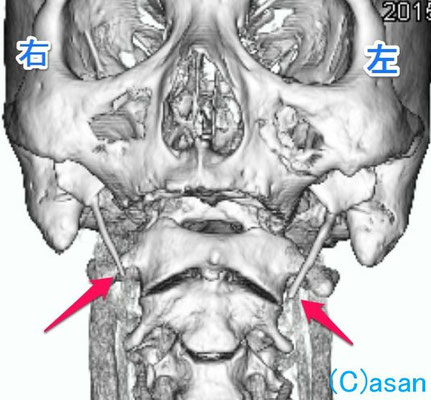

こちらは、飲み込む時に、喉の左側に違和感と痛みがあるとのことで受診された方です。 MRIや胃カメラを受けてこられたものの異常がありませんが、喉の奥を指で触ると左側に特に硬い突起が触れました。CTで茎状突起過長症という診断です。

茎状突起は誰でも持っている、動物で言うと牙のような骨の突起ですが、これが生まれてから成長するうちに、片方あるいは両側、より長くなったものです。

この方はご年配の方ですが、何かのきっかけでこれが気になるようになったものと思います。CTの写真をお見せしご説明すると、1‐2ヶ月で症状は気にならなくなったとのことです。

ただし、痛みが強く、続くようであれば、手術で粘膜を切って、突起の先端を切り落とすこともあります。